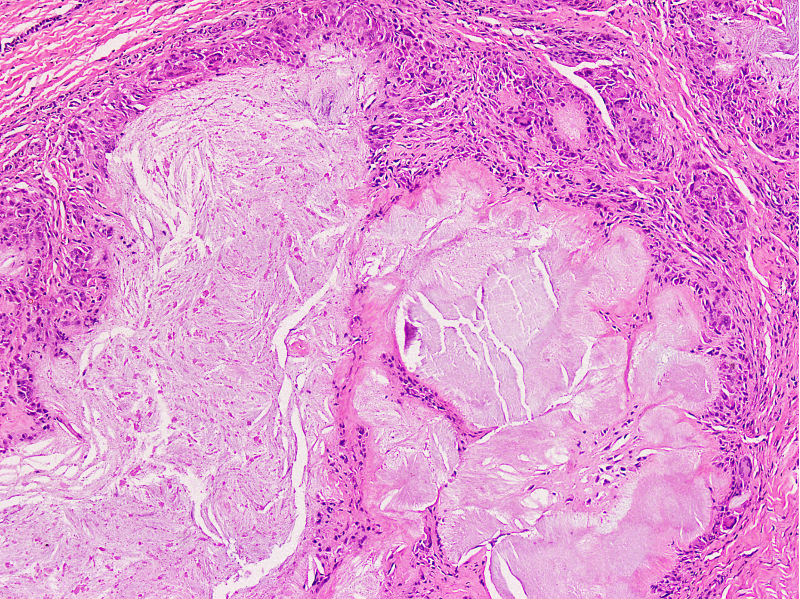

Microscopic (histologic) description

- Gout tophus:

- Nodular aggregates / granuloma-like appearance consisting of acellular, amorphous, pale eosinophilic material surrounded by palisading arrangement of histiocytes and multinucleated giant cells (Dermatol Online J 2015;21:13030)

- Feathery appearance in some deposits due to empty needle shaped spaces (Skeletal Radiol 2020;49:1325)

- Presence of monosodium urate crystals (MSU) is diagnostic

- Needle-like crystals that measure 5 - 25 micrometers in length

Microscopic (histologic) images